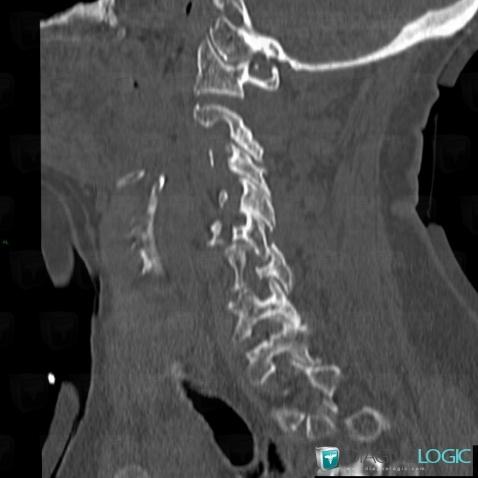

The images below illustrate this case for diagnoses Dislocation, Vertebral fracture, for the modalities (CT)

- Diagnosis Vertebral fracture, Location(s) Vertebral body / Disk, with gamuts

- Diagnosis Dislocation, Location(s) Vertebral body / Disk, with gamuts